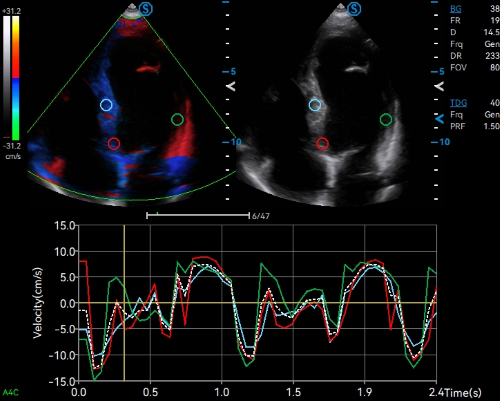

· Tissue Doppler Imaging Quantitative Analysis (TDI QA) supports quantitative analysis for myocardial motion with multiple sampling points